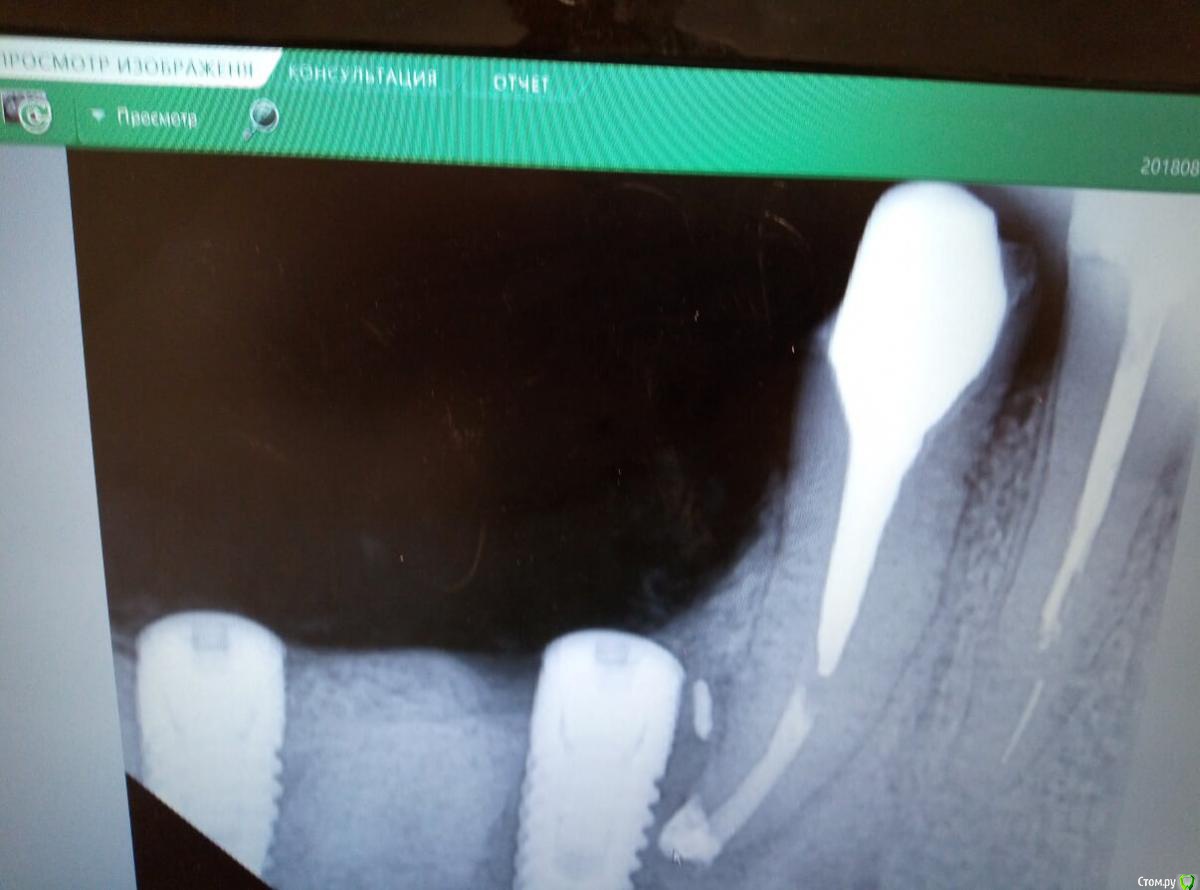

Колосс Опубликовано 16 февраля, 2019 Поделиться Опубликовано 16 февраля, 2019 Удалили и заново поставили 2 импланта.Причиной предыдущего удаления был свищ из соседнего зуба, который вовремя не был определен и который снова после повторной имплантации вылез рядом с имплантом.Гнойник надувался каждый день. Зуб залечили, после промывания гной перестал идти, но свищевой ход пока не зарос. Выкладываю фото с моментального снимка. Прошу консультацию.Побежден ли свищ и будет ли жить имплант.Если можно, прошу отвечать подробнее.Доктор настроен оптимистически, но я опасаюсь.Если снимок недостаточно информативен, сделаю орто. Заранее спасибо. Ссылка на комментарий

chervoncevdaniil Опубликовано 16 февраля, 2019 Поделиться Опубликовано 16 февраля, 2019 (изменено) Я оптимизма доктора не разделяю,орто или срезы кт было бы информативнее Изменено 16 февраля, 2019 пользователем chervoncevdaniil 1 Ссылка на комментарий

Колосс Опубликовано 16 февраля, 2019 Автор Поделиться Опубликовано 16 февраля, 2019 Я оптимизма доктора не разделяю,орто или срезы кт было бы информативнееОрто сделаю как можно быстрее Пока можно поделиться предположениямиГной от свища пошёл в имплант? Ссылка на комментарий

red_butler Опубликовано 17 февраля, 2019 Поделиться Опубликовано 17 февраля, 2019 Орто сделаю как можно быстрееПока можно поделиться предположениямиГной от свища пошёл в имплант?давайте дождемся вашего снимка 1 Ссылка на комментарий

Колосс Опубликовано 17 февраля, 2019 Автор Поделиться Опубликовано 17 февраля, 2019 Выкладываю снимок Ссылка на комментарий

Колосс Опубликовано 17 февраля, 2019 Автор Поделиться Опубликовано 17 февраля, 2019 Выложил снимок, ниже в сообщении Ссылка на комментарий

johniola Опубликовано 17 февраля, 2019 Поделиться Опубликовано 17 февраля, 2019 убирайте имплант 5 Ссылка на комментарий

red_butler Опубликовано 17 февраля, 2019 Поделиться Опубликовано 17 февраля, 2019 +1 удалять 3 Ссылка на комментарий